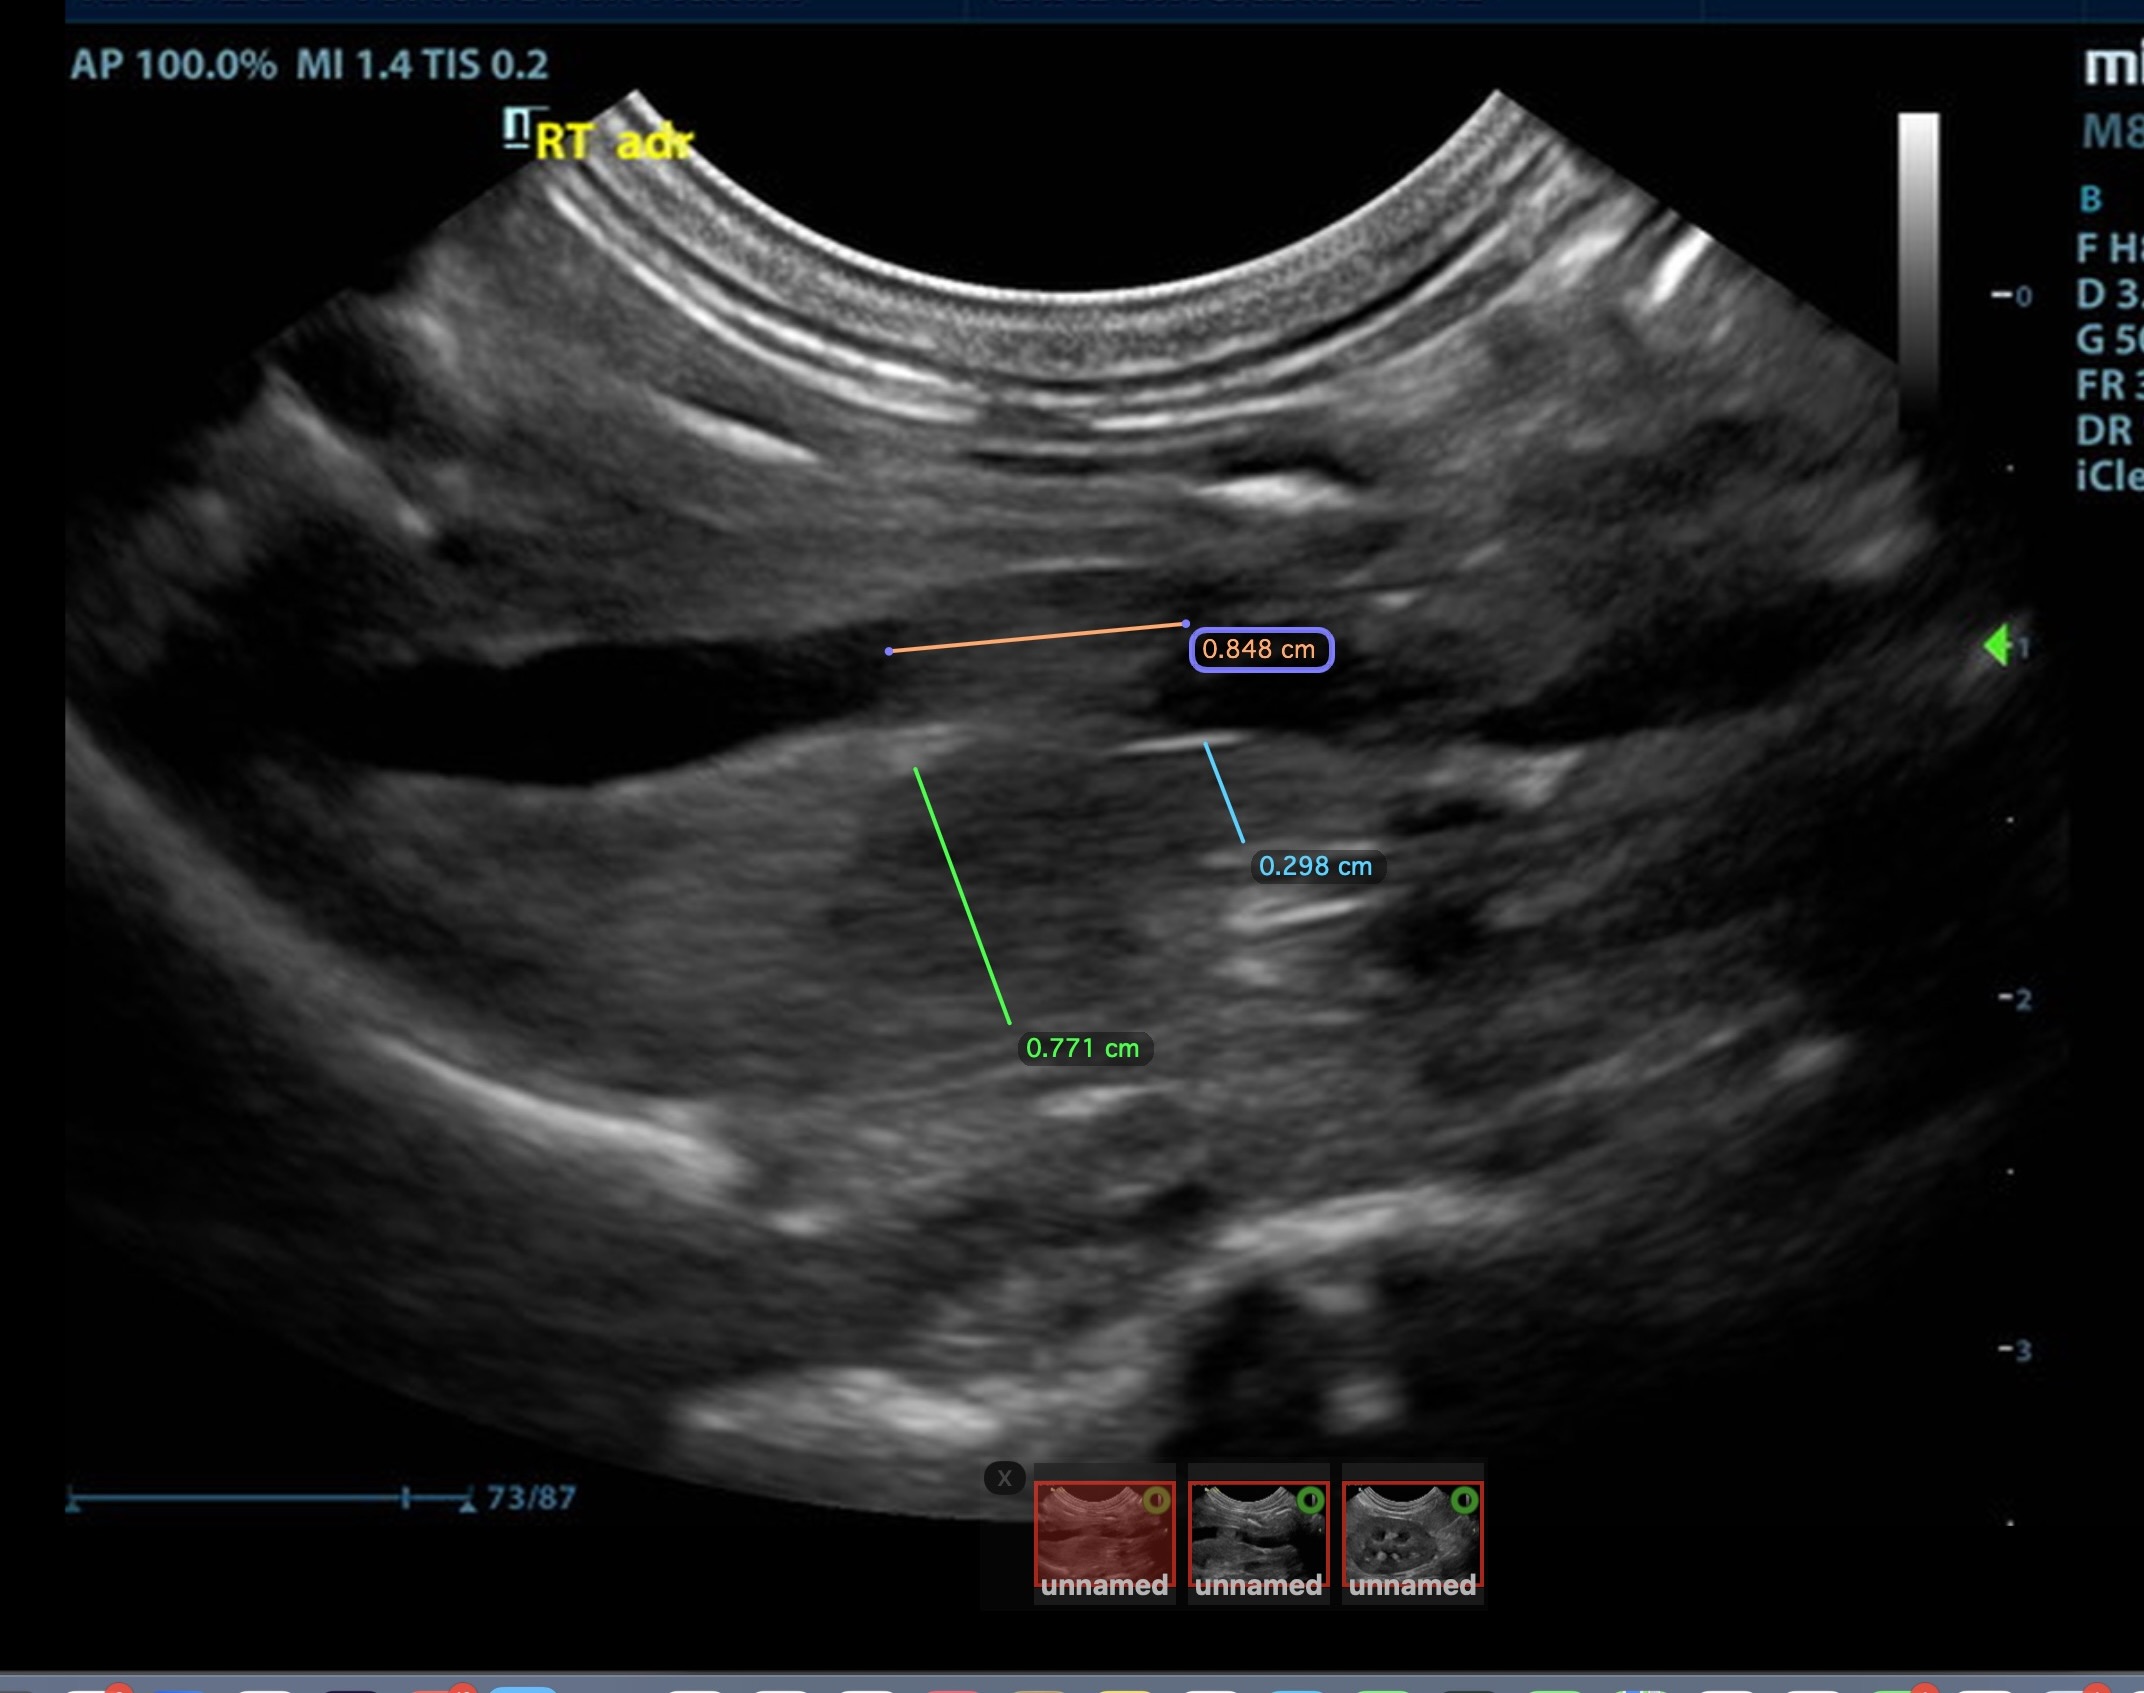

The right adrenal was enlarged and irregular, measuring 0.77 cm at the cranial pole and 0.30 cm at the caudal pole, with a caval invasion of 0.85 cm. Minor areas of mineralization noted. The left adrenal gland was recognized as normal. Mild variable GI thickening and echogenic submucosal changes. Some loss of renal curvilinear patterns regarding the capsule and cortico-medullary junction; increased echogenicity, mineralization.  Some hepatic parenchymal remodeling.

• Invasive right adrenal mass